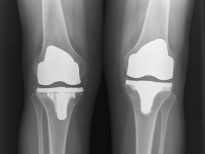

在周主任安排下,陆大娘在住院的第三天手术,第一次手术先做症状严重的右侧膝盖,3个月后再做另一侧膝盖,这样康复效果会更好一些。手术由周军杰主任医师亲自主刀,在麻醉科协同合作配合下,实施全身麻醉右侧人工全膝关节置换+膝关节松解术,手术采取微创膝关节前侧直入路,手术历时约85 min,手术中出血量少于50ml。手术后第2天即可自行扶拐下地行走、功能锻炼。术后3周患者已能自行行走,膝关节活动功能恢复良好,陆大娘对疗效十分满意。

第一次手术后2个月陆大娘就迫不及待地来找周主任,要求做另一侧的膝盖手术,同样,手术还是由周军杰主任医师亲自主刀,第二次手术相对症状较轻,手术在更短的时间内就完成了,手术后的恢复也是一样的顺利。手术后3个月,陆大娘就已经能生活完全自理,并且又能完全照顾老伴的起居了!两次手术,两个膝关节置换手术和功能康复,前后不到5个月,陆大娘困扰了数年的难题就都解决了。

人工膝关节置换

人工膝关节置换是终末期骨性关节炎最有效的治疗手段。适用于60岁以上、膝关节有严重病变,或伴有反复发作的关节疼痛、肿胀、畸形和关节不稳,严重影响日常生活,经保守治疗无效或效果不明显的就必须采用人工膝关节置换手术。当然现在针对膝关节单间室(内侧或外侧)的病损也可以采用人工单髁膝关节表面置换手术。